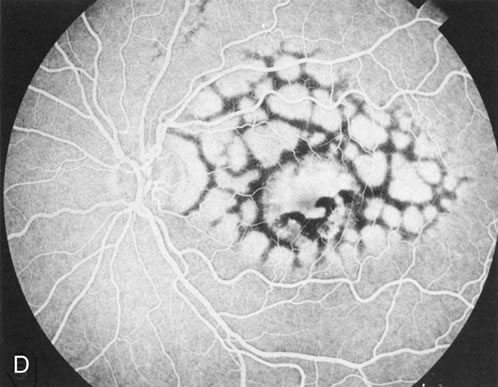

Fig. 4. Choroideremia and choroideremia carrier. A. The choroidal atrophy in this affected male is not apparent in the fundus. B. However, the angiogram shows diffuse atrophy of the choriocapillaris with persistent visualization of the larger choroidal vessels. C. This carrier female has peripapillary choroidal atrophy and diffuse pigment mottling. D. The patchy areas of focal choroidal atrophy that occasionally occurs in carriers is evident on angiography.

The typical carrier female, with focal or diffuse pigment mottling, does not show choroidal atrophy. However, a few carrier females have a more severe form with focal areas of choroidal atrophy. The presence of these areas, and possible progression, can be documented by FA (Fig. 4C and D). These carriers exhibit a mosaicism, which is explained by the Lyon hypothesis of random X-chromosome inactivation.